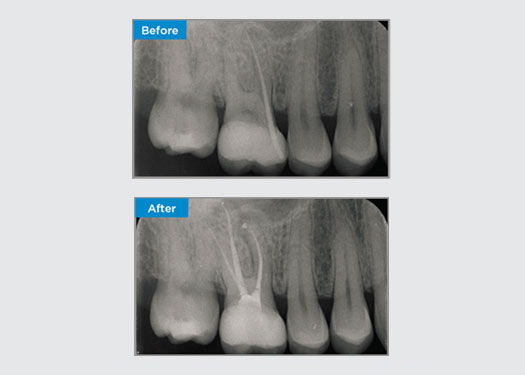

Le patient présentait une parodontite apicale asymptomatique sur la dent 34. Sur la radiographie préopératoire, la dent 34 était notée avec deux racines visibles. Cependant, un scanner CBCT a confirmé une prémolaire à trois racines, les canaux se divisant en trois au milieu de la racine. Une sélection minutieuse des limes est essentielle pour cette dent délicate.

Dr Jack Lin, endodontiste, Sydney, NSW Australie

Dans cette situation, la préservation de la structure de la dent/racine est essentielle pour réduire le risque de déviation, de transport, de radiculalgie, de perforation et de fracture de la racine. La sélection des cas, le diagnostic et la planification avant le traitement sont importants. La sélection de limes endodontiques avec flexibilité, efficacité et respect de l’anatomie naturelle de la racine est essentielle.